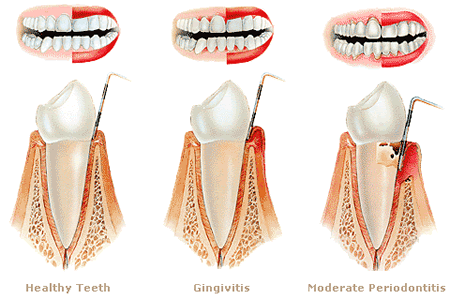

When gums bleed during brushing, the soft gum tissue is inflamed and irritated. Healthy gums are firm, pink, and do not bleed even with regular brushing.

Gingivitis is the leading cause of bleeding gums worldwide. It is the early stage of gum disease caused by plaque buildup along the gum line.

When plaque — a sticky film of bacteria — is not properly removed, it irritates the gum tissue. This leads to redness, swelling, and tenderness.

When gingivitis is left untreated, it progresses to periodontitis. This is a serious and more destructive form of gum disease.

Periodontitis damages the connective tissue and bone that hold teeth in place. Symptoms include deep gum pockets, gum recession, and loose teeth.

At this stage, bleeding gums are a regular symptom. Treatment requires professional deep cleaning called scaling and root planing, and sometimes surgery.